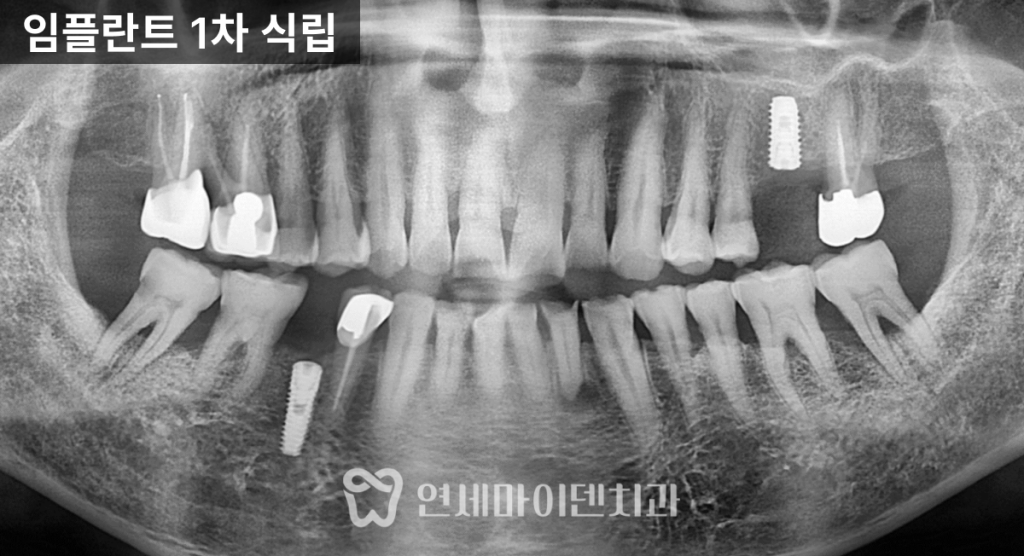

오랫동안 건강하게 유지될 수 있습니다.3D 가이드 임플란트 계획

임플란트는

뼈와 잇몸의 상태를 고려해

정밀하게 설계되어야 하는 치료입니다.

수술 전 3D CT 촬영을 통해

임플란트 식립 위치와 각도를

미리 계획했고,

주변 해부학적 구조물을 피하면서

안정적인 식립이 가능하도록 준비했습니다.

또한 염증 발생 가능성을 낮추기 위해

이번 케이스에서도

임플란트 픽스처를

뼈 레벨보다 약간 안쪽으로 식립해

안정성을 높였습니다.건강보험 임플란트 최종 보철

기능을 회복할 수 있었습니다.6년 경과, 보험 임플란트 장기 결과

치료가 끝난 이후에도

정기적인 검진과 관리는

매우 중요합니다.이번 케이스는

6년 이상 장기 추적 관찰을 진행했습니다.치료를 받지 않았던 일부 치아는

시간이 지나면서

추가 임플란트가 필요하게 되었지만,초기에 임플란트를 식립한 부위와

앞니 레진 수복 부위는

큰 문제 없이

안정적으로 유지되고 있었습니다.건강보험 임플란트 제도는